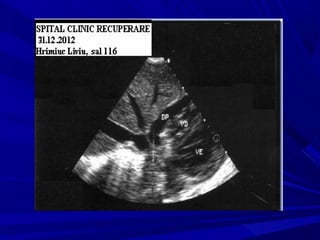

CASE No 1CASE No 1

age: 41age: 41

Hrimiuc LiviuHrimiuc Liviu

ANAMNESYSANAMNESYS

Thoracic pain for 3 weeksThoracic pain for 3 weeks

Physical examination – pericardial rubPhysical examination – pericardial rub

EKG –ischemia ?EKG –ischemia ?

Echo –pericardial fluidEcho –pericardial fluid

ECHO-CARDIOGRAPHYECHO-CARDIOGRAPHY